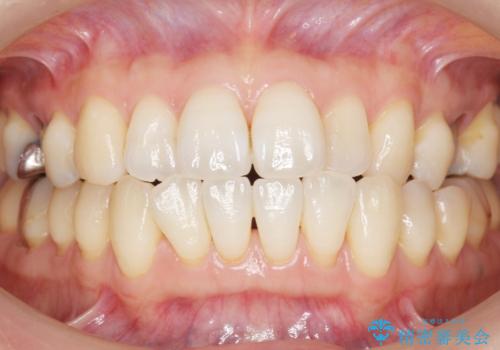

自然な見た目と咬み心地にご満足頂けました。

オフィスホワイトニングを行い、白くなった天然歯に合わせたシェード(お色味)でクラウンを作製しました。